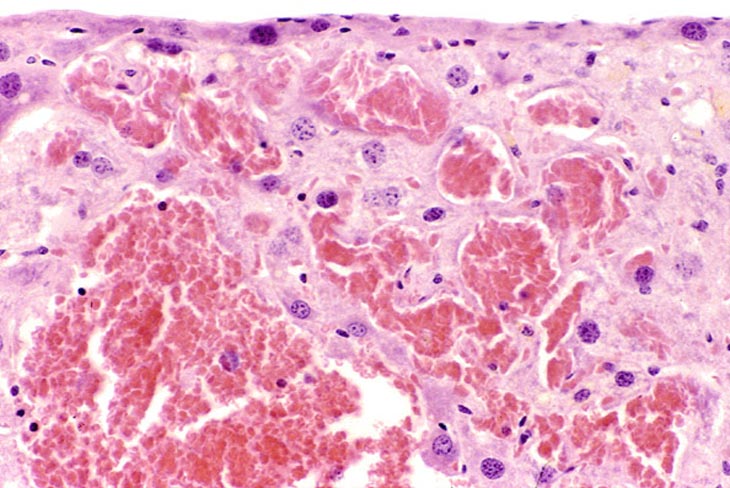

These examples represent medium magnification views of angiectasis.

These examples represent high magnification views of angiectasis.